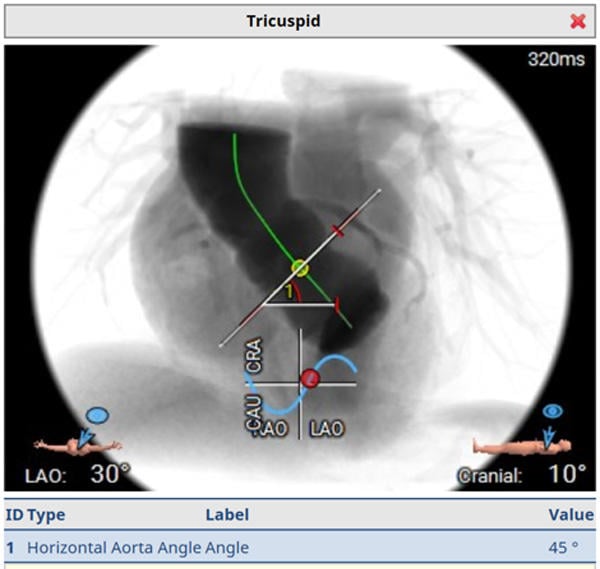

Computed tomography

- 68-year-old woman with symptomatic aortic valve stenosis and tricuspid valve anatomy